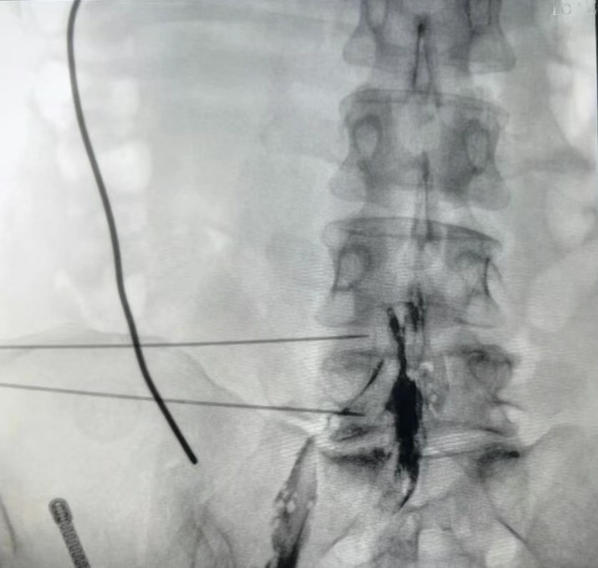

腰椎间盘射频消融联合胶原酶化学溶解术后